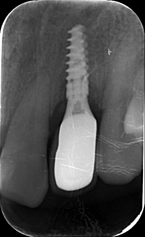

术后4.5个月根尖片

ISQ动度值颊舌/近远中为70/73。

戴牙后20天复查X线检查